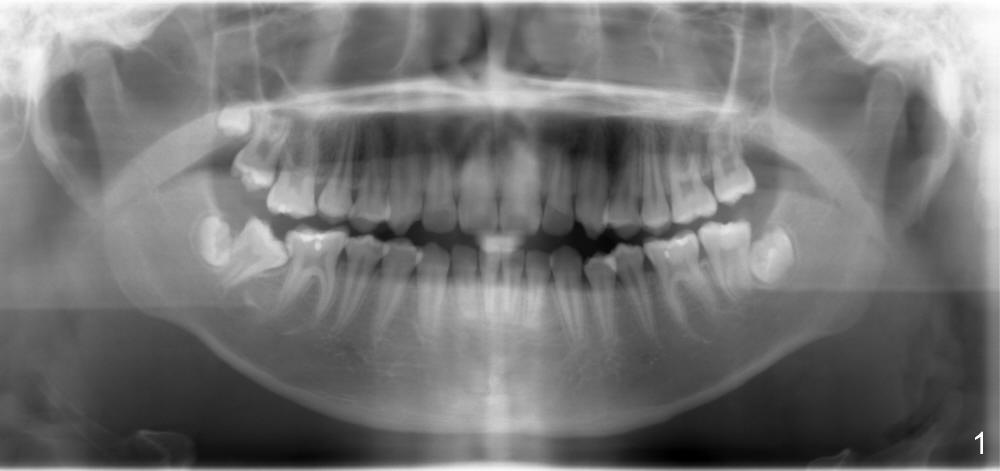

How are you lately?  The tooth #31 is mesioangularly impacted (13 year old fully developed boy).  Is it be able to be auto corrected?Do you recommend extracting #32 before orthodontic treatment?  Thanks.

It will not auto correct. I like the idea of extracting #32 before treatment.

Then, if you can get a bracket on #31 at the proper angulation, you will upright the tooth in a hurry. If you cannot get a bracket on the tooth, then I ask the surgeon to place an interdental wire between 30 and 31 to treat as a separator first and/or ask for mild luxation/elevation of #31.